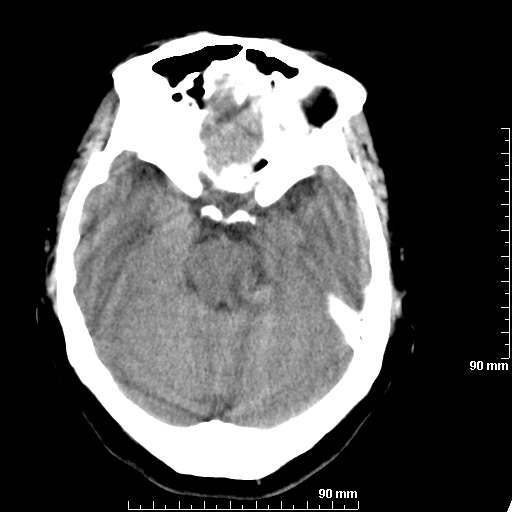

我院西门子单排CT由于一零件受损而产生的伪影.

哈哈,都不是。是虑线器fiter裂损。大家没想到吧。

哦,跟脑出血有点像哦

形状不规则,边缘模糊。比较特殊的一种伪影哈!

这种伪影很常见!伪影应该是在视野的中心的。

西门子的虑线器fiter裂损这才是很难见的问题,GE的最常见

虑线器老化,中间崩裂一块掉了